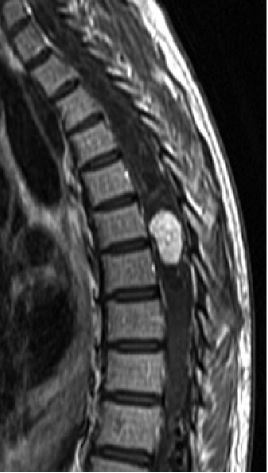

18

Q

-modality -weight -orientation -body part -contrast -abnormality

A

-MRI - T1 -sagittal -thoracic spine -yes -hemangioblastoma